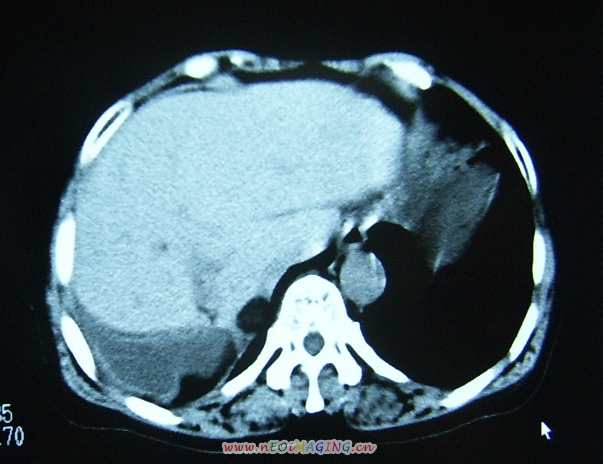

标题: CL0653:【】异位胆囊 [打印本页]

标题: CL0653:【】异位胆囊

女56y右上腹不适数年.

异位胆囊